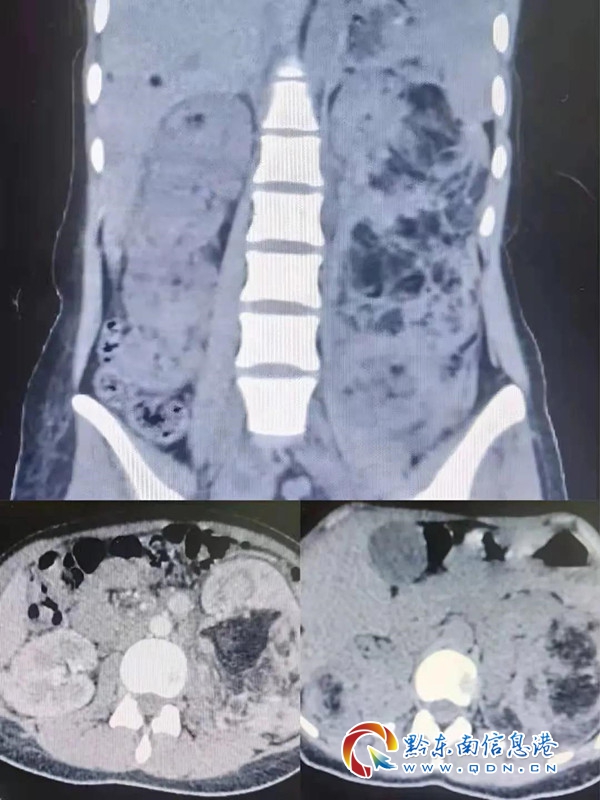

第三位患者小蘭,24歲,因突發左側腰痛入院,小蘭面部三角區有明顯的對稱蝴蝶斑樣皮脂腺瘤樣改變,腹部左右均有包塊。由于疾病罕見,楊佐炎主任組織了MDT討論,最終確定診斷為結節性硬化癥合并左腎腫瘤自發性破裂出血,如果不及時手術,隨時有可能大出血危及生命。隨后泌尿外科二病區團隊于2月5日予患者進行了“經腹腔開放性左側腹腔腫瘤剜除術”手術治療,最大限度的保留殘余腎臟,延長患者生存時間,手術切除左腎巨大包塊3個,最大直徑約12Cm,目前該患者生命征平穩。